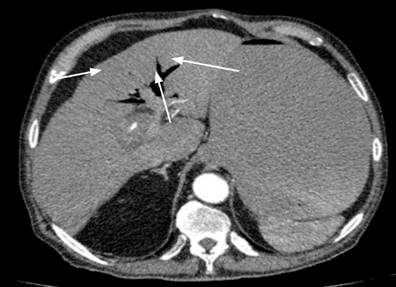

Durante la hospitalización presentó deterioro del estado general y se sospechó de sepsis de origen biliar, por lo cual decidieron llevarlo a manejo en la unidad de cuidados intensivos (UCI). El reporte de tomografía abdominal no permitió una adecuada definición de vesícula biliar, mostraba una imagen en diana y collar de perlas, sugestivas de obstrucción intestinal mecánica, asociada con intususcepción e isquemia intestinal con una importante distensión de asas delgadas (Figura 1); adicionalmente, se observó una imagen de neumobilia intrahepática (Figura 2), por lo cual se realizó una laparotomía exploratoria y se encontró una obstrucción intestinal a 170 cm del ángulo de Treitz por cálculo biliar ojival de 6 * 4 cm (Figura 3), se hizo una enterolitotomía sin corrección de fístula colecistoentérica en el primer tiempo quirúrgico durante el cual requirió la colocación del sistema de cierre asistido por vacío (VAC) secundario a evisceración por una importante distensión de asas intestinales.

Figura 1 A y B. Imagen en diana de tomografía abdominal sugestiva de obstrucción intestinal por intususcepción. C. Imagen de collar de perlas sugestiva de obstrucción intestinal. Imágenes propiedad de los autores.